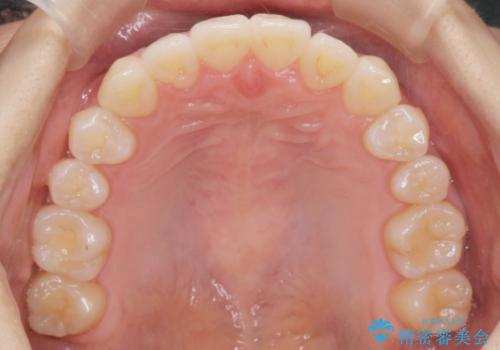

- 噛んだ時の前歯正中のズレ、引っ込んでいる前歯を治したい。と矯正治療を希望され来院されました。

左上2の前歯はスペースが足りないため、後方に引っ込んでしまっている状態です。

マウスピース矯正システムインビザラインで歯の後方移動、咬合関係の修正を行ったのち、引っ込んでいる左上2をワイヤーを用いて短時間で引き出す治療計画としました。